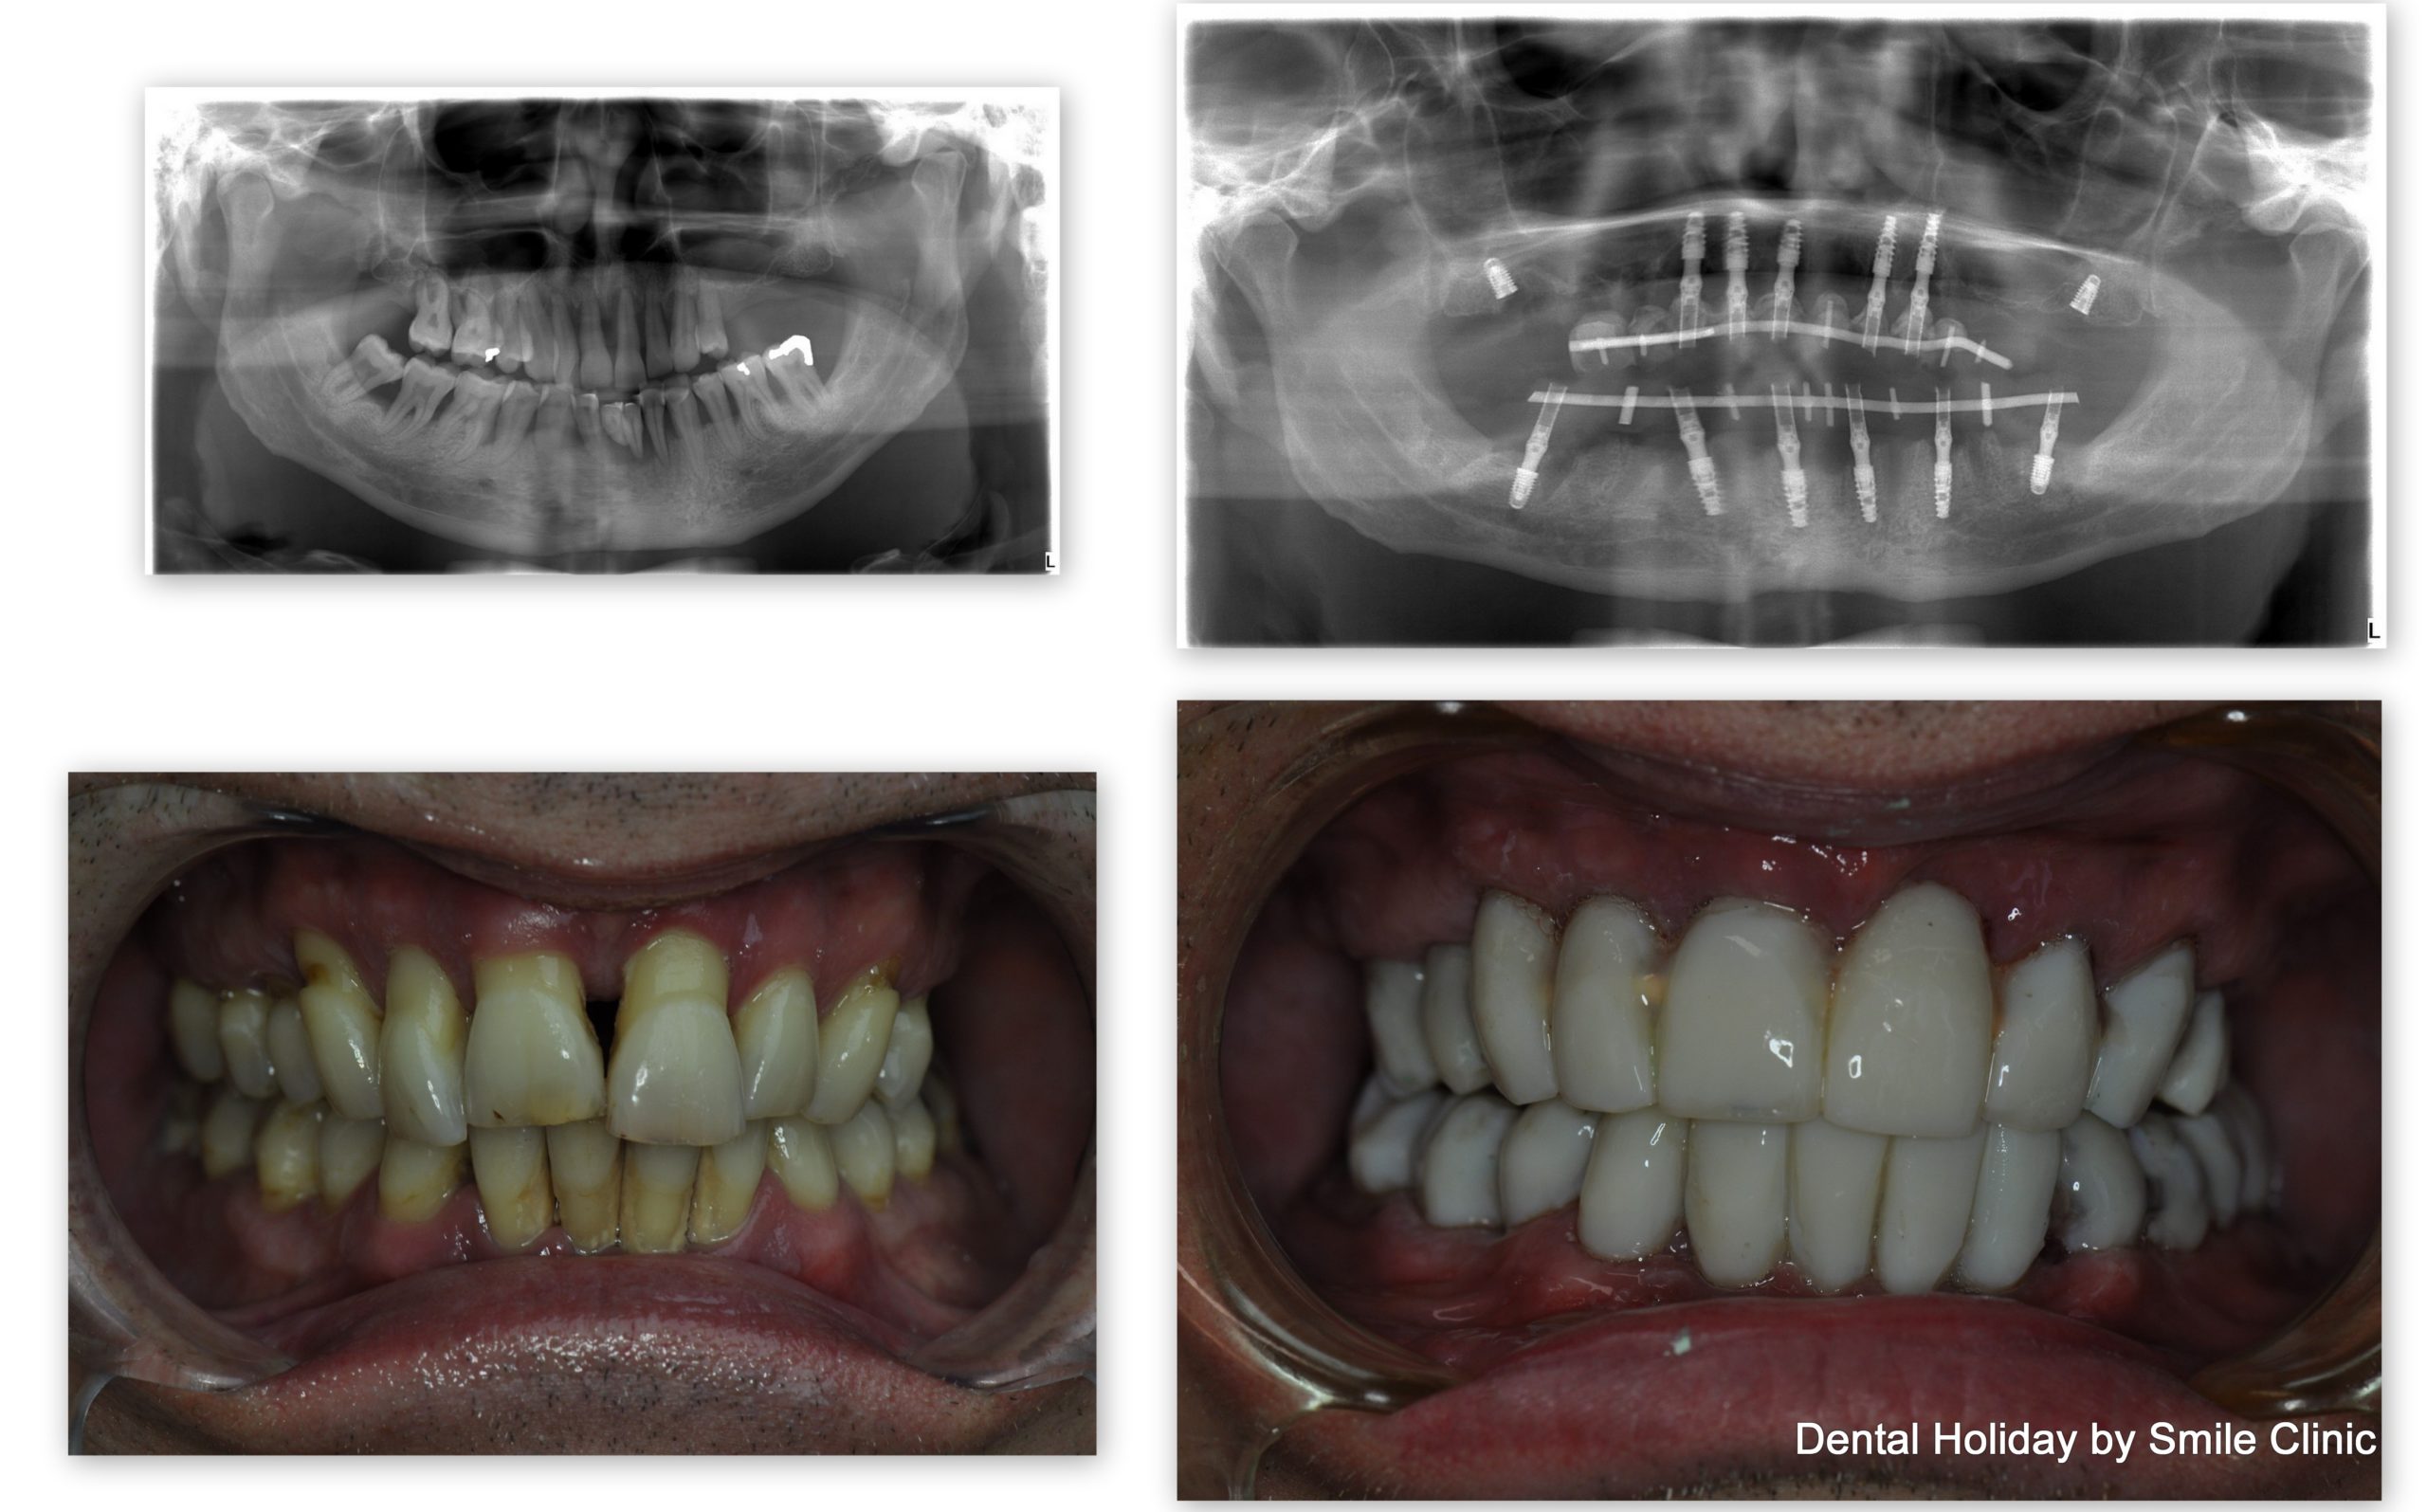

He started his dental treatment with us just before Christmas 2015 and by April 2016 his full mouth reconstruction of the upper and lower teeth was successfully completed.

As you can see on the x-ray here, this included 14 implants and 28 crowns in total, as unfortunately most of his teeth were loose. As you can see from the photographs, the final results provided a fixed, balanced smile, with no worry of ever having to wear a dreaded denture.

In the picture collage you can see the immediate change from loose unstable teeth to permanent fixed temporary bridges: